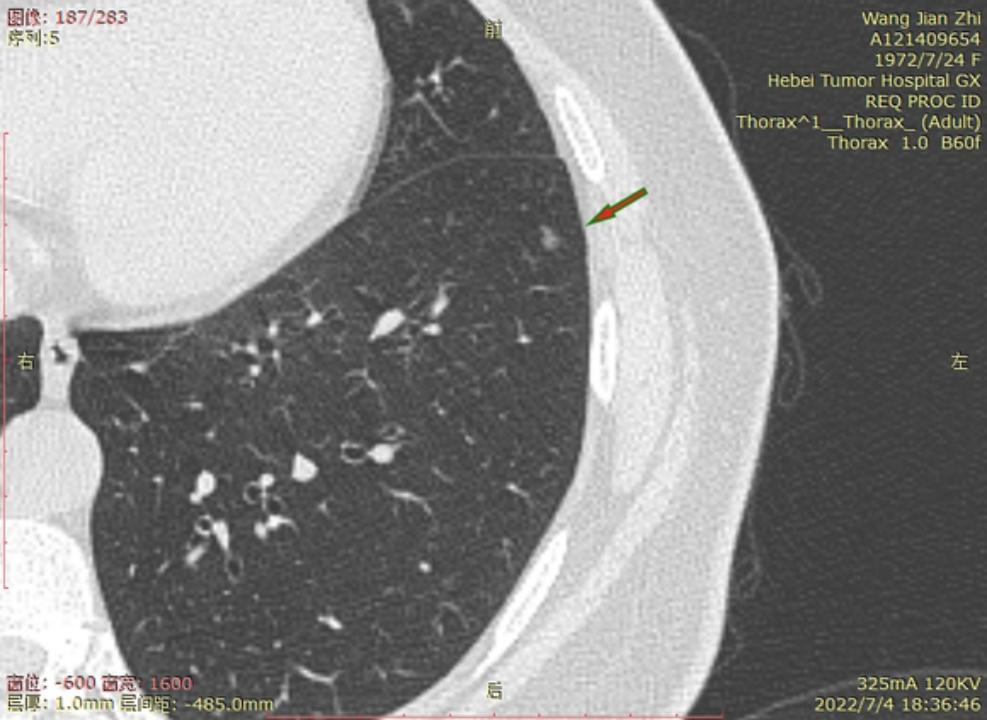

今年6月22号河北省人民医院进行CT检查后,报告双肺多发磨玻璃结节及微小结节以右肺为多,建议六个月后复诊。我于7月3号在河北省四院胸外科就诊,大夫建议复查薄层CT,7月4日CT结果报告示两肺多发结节,部分为磨玻璃密度,建议三个月复查,省四院的主任看了CT后有的建议立即住院手术,有的建议三个月复查,专家意见不一致,后来我看了主任的贴吧,首次发现肺结节先口服莫西沙星,三个月后再复查的贴吧,就没有立刻手术,从7月4日开始口服莫西沙星,现已完成15天疗程。等待复查的这一段时间里,总是担心大的结节已有浸润,请主任给予帮助,看看我的CT,给出我治疗建议,麻烦主任了!

右侧至少5枚以上的微浸润或原位腺癌,大的两枚结节微浸润,建议半年内把右侧5mm以上或者有危险的结节一网打尽。左侧结节还安全,安心随访

结4-5